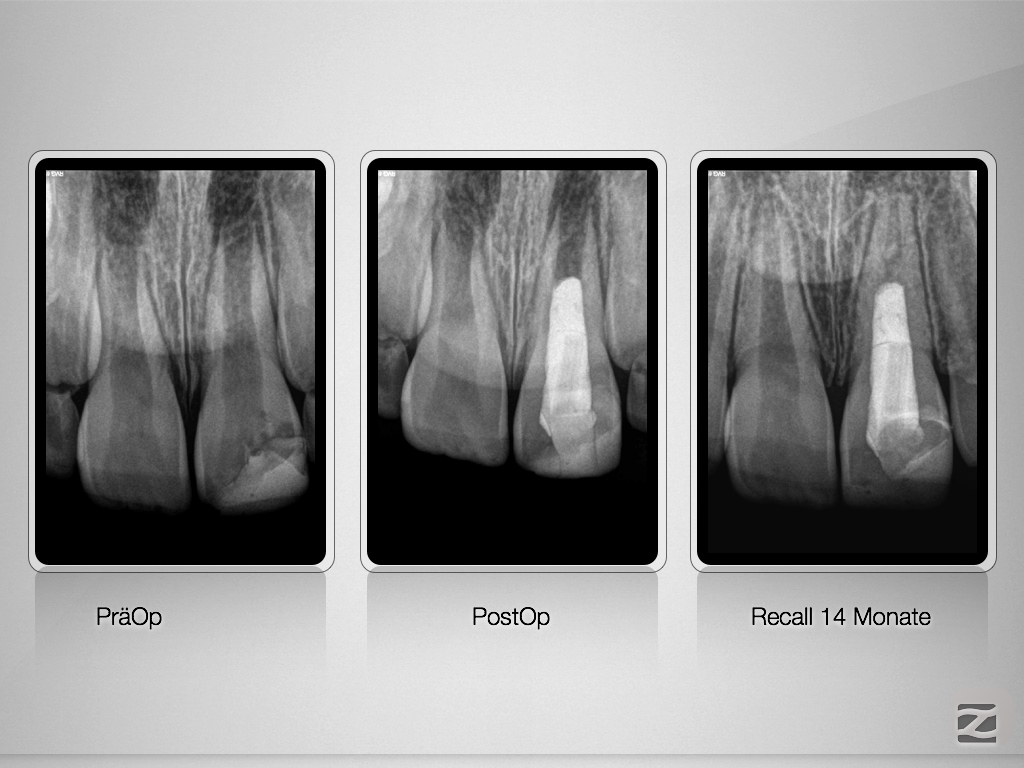

Tiefe Pulpotomie – das Recall